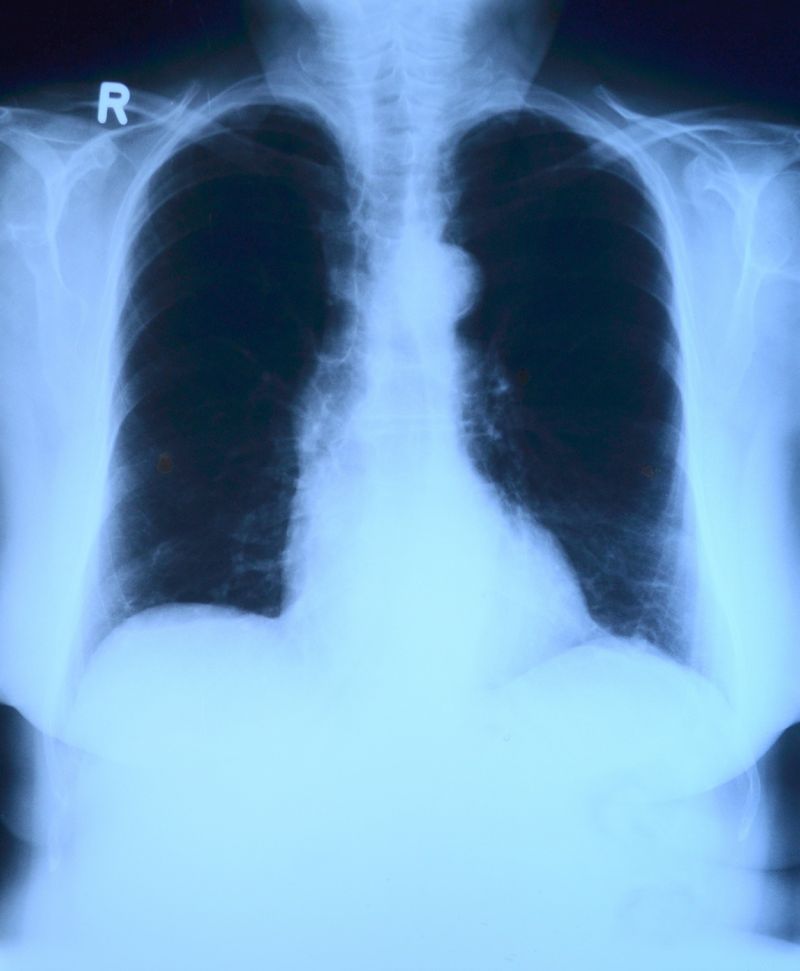

Plămâni

Plămâni [Sursa foto: PixaBay]